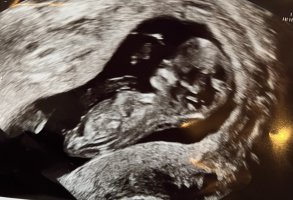

12+0, jordmor sa hun så kjønn. Men ville ikke si noe. Så spent :Heartred

Her er vårt litt nurk fra i dag. Flyttet fire dager frem. Alt så fint ut. Både jordmor og jeg føler oss ganske sikre på at det er en gutt. Sprella og koste seg. Var veldig betryggende etter mange uker uten andre symptomer enn voksende mage. Kom ei pittelita tåre i øyekroken.

13+1 i dag da.